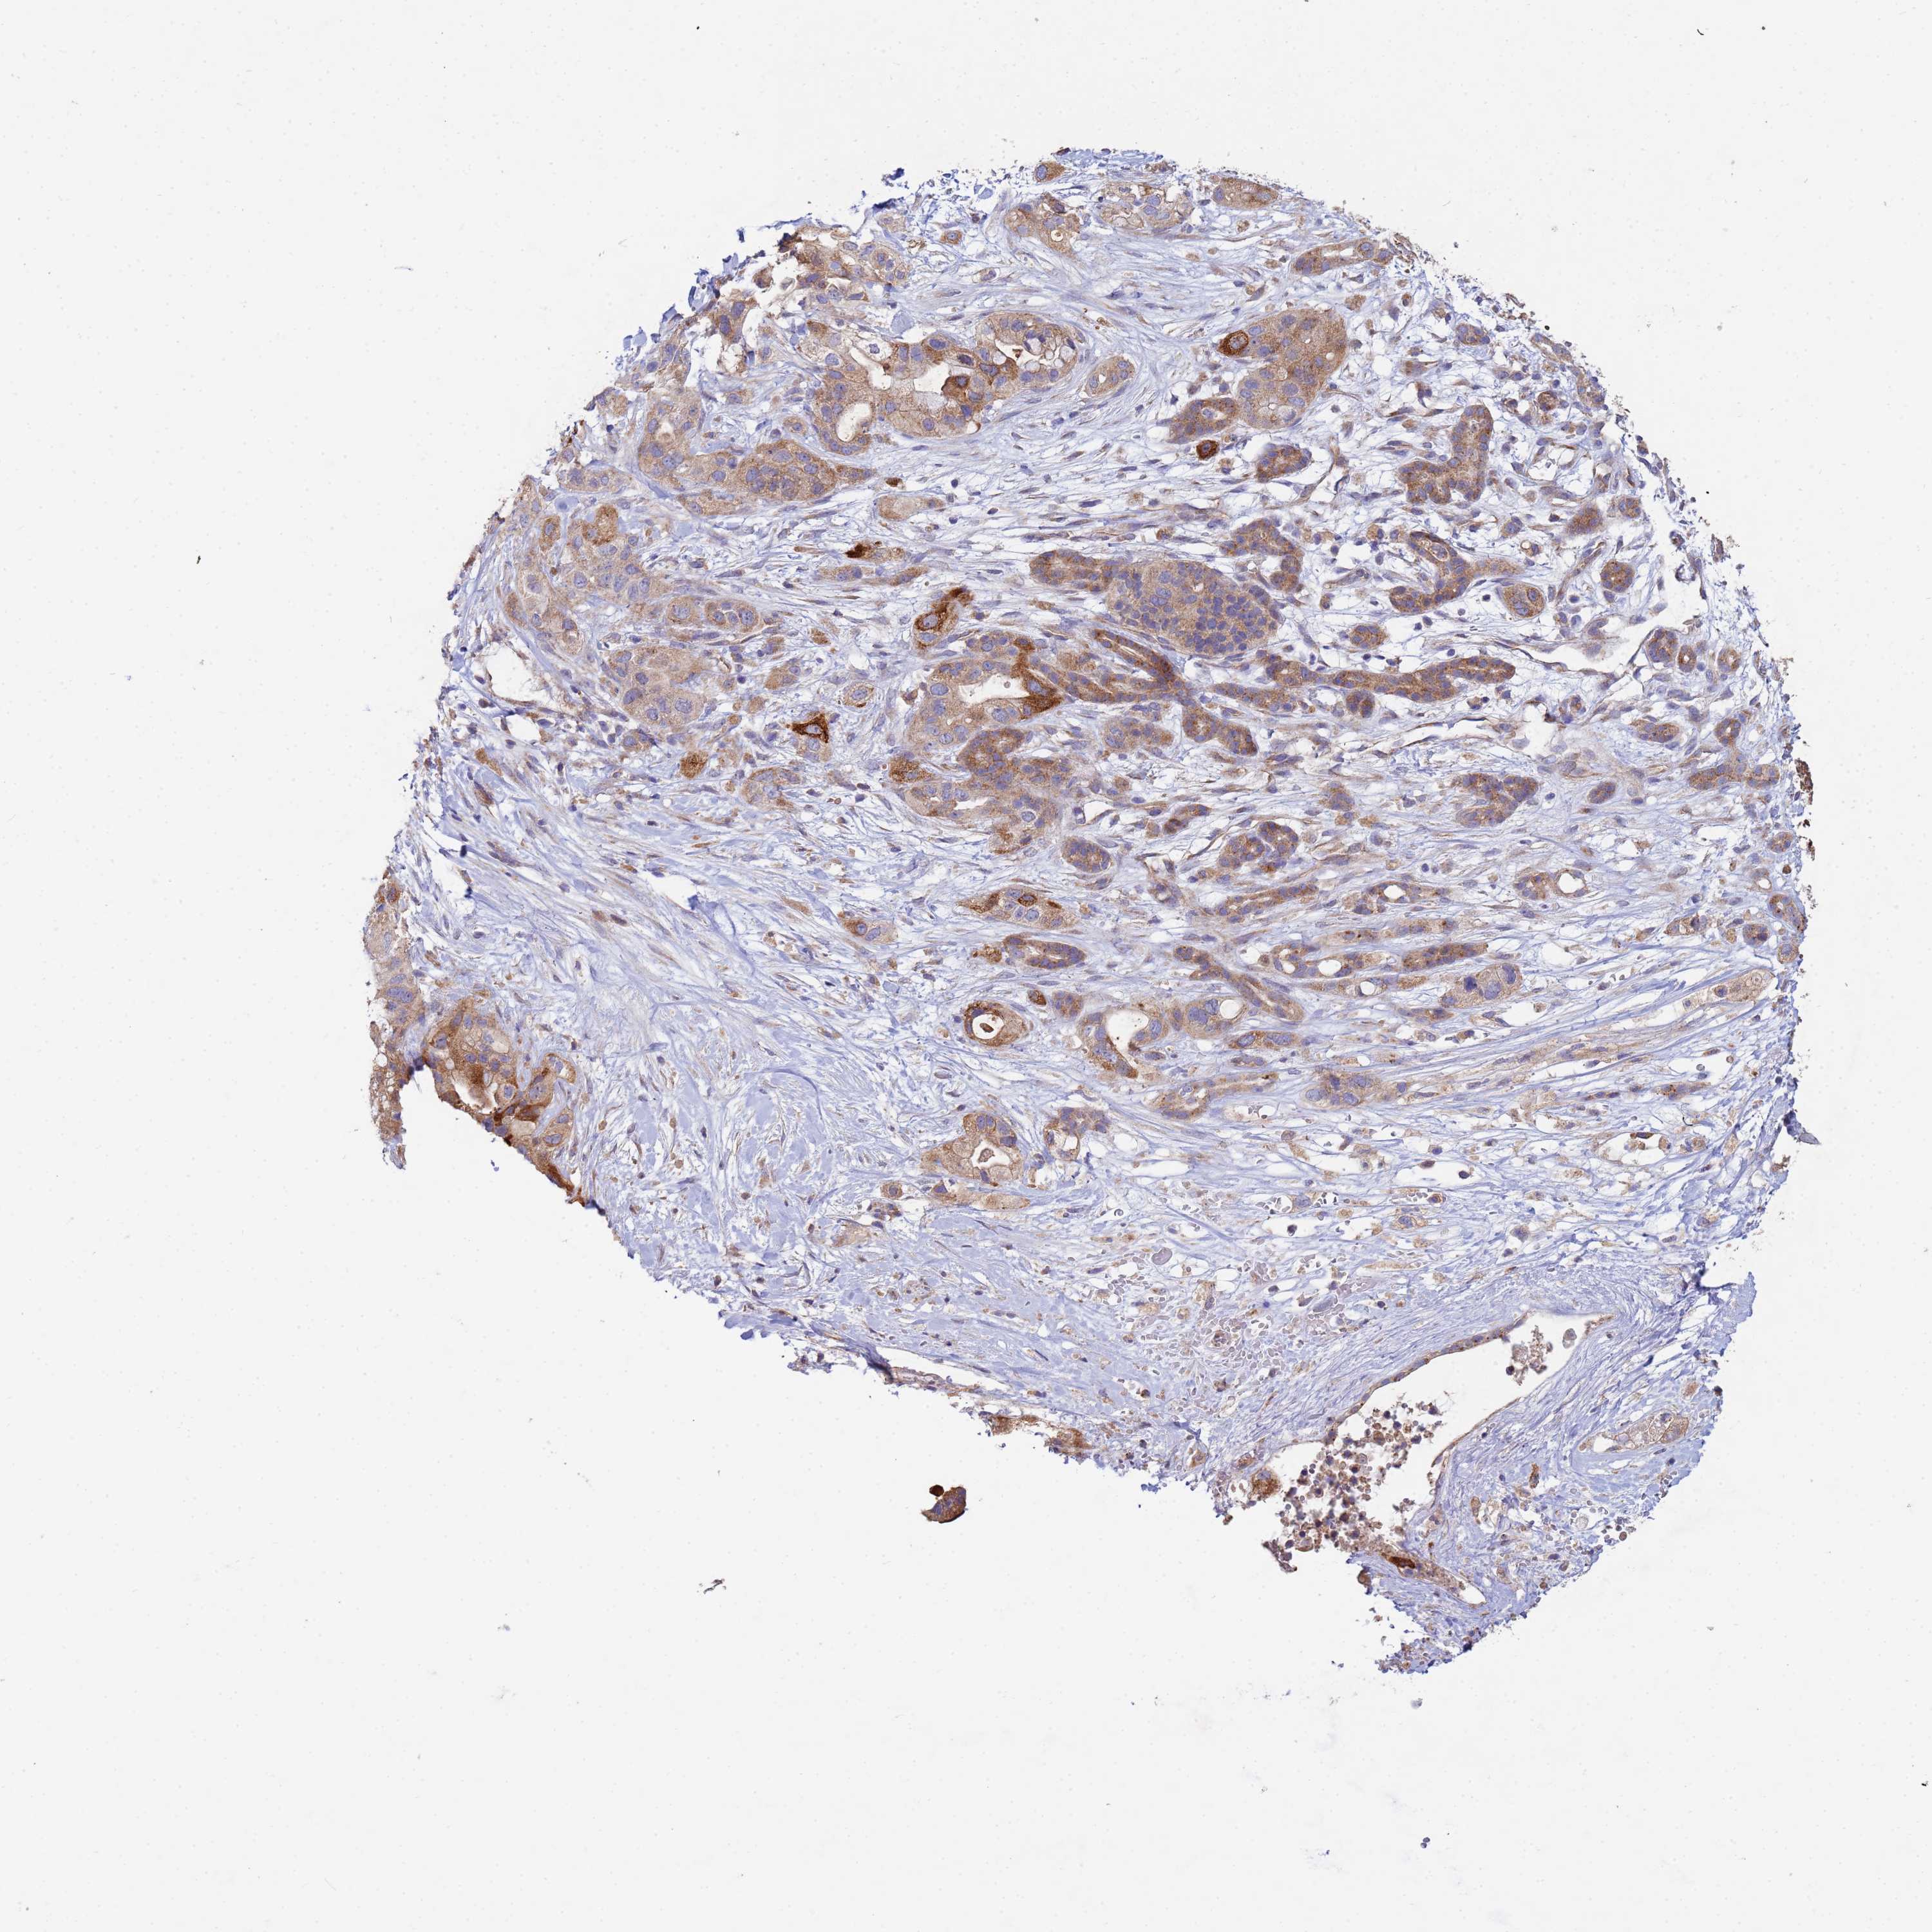

PANCREATIC CANCER - Protein expressioni

A mouse-over function shows sample information and annotation data. Click on an image to view it in a full screen mode. Samples can be filtered based on level of antibody staining by selecting one or several of the following categories: high, medium, low and not detected. The assay and annotation is described here.

Note that samples used for immunohistochemistry by the Human Protein Atlas do not correspond to samples in the TCGA dataset.

Antibody stainingi

Antibody staining in the annotated cell types in the current human tissue is reported as not detected, low, medium, or high, based on conventional immunohistochemistry profiling in selected tissues. This score is based on the combination of the staining intensity and fraction of stained cells.

Each image is clickable and will lead to virtual microscopy that enables deeper exploration of all samples and also displays staining intensity scores, fraction scores and subcellular localization as well as patient and tissue information for each sample.

Antibody HPA002382

Antibody CAB005109

Antibody CAB047311

Staining

High

Medium

Low

Not detected

Intensity

Strong

Moderate

Weak

Negative

Quantity

>75%

75%-25%

<25%

None

Location

Nuclear

Cytoplasmic/membranous

Cytoplasmic/membranous,nuclear

Adenocarcinoma, NOS

Adenocarcinoma, metastatic, NOS